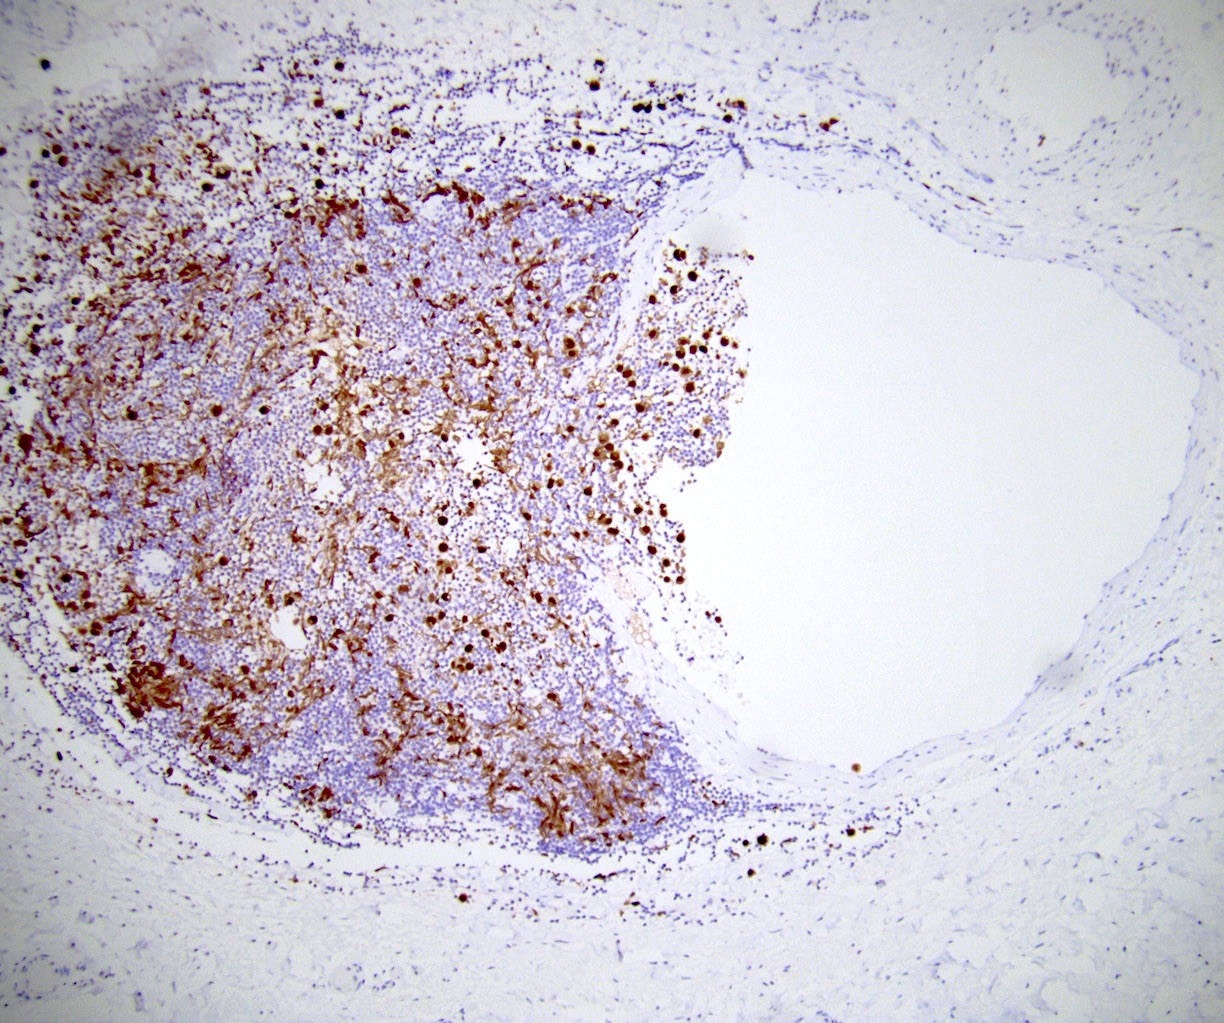

Microscopic (histologic) images

Board review style question #1

In a postpubertal testicular germ cell tumor, lymphovascular (shown above), hilar fat, epididymal and tunica vaginalis invasion are all a part of which pT category?

Board review style answer #1

D. pT2. Lymphovascular, hilar fat, epididymal and tunica vaginalis invasion are all a part of the pT2 category for testicular germ cell tumors. Lymphovascular invasion by embryonal carcinoma is shown in the image.

Comment Here Reference: